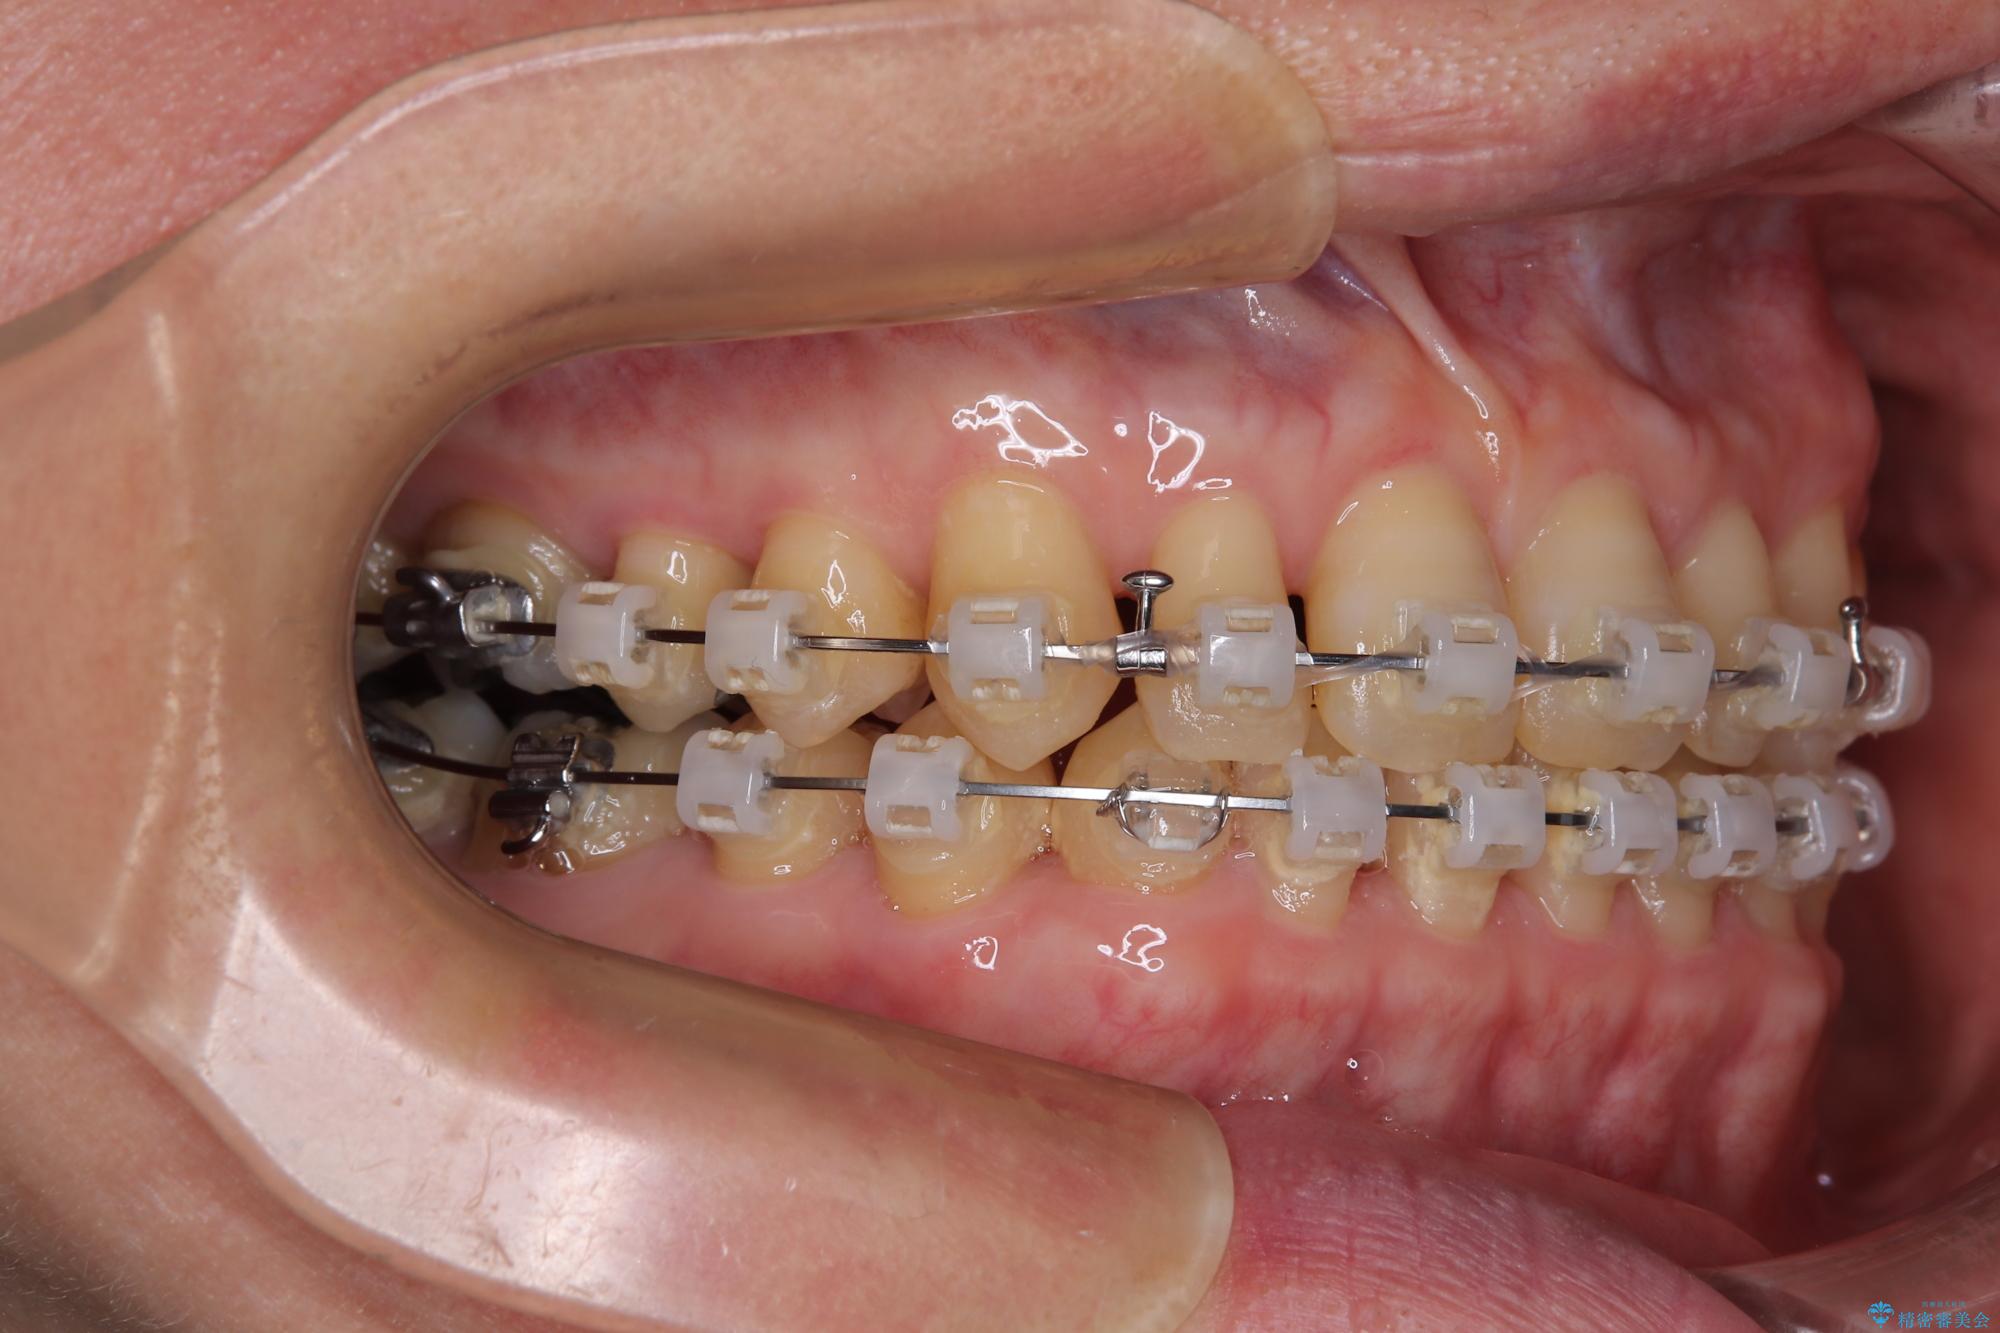

- 矯正装置

- クリアブラケット

下顎前歯が隠れるほどのディープバイトにより、強い咬合力と突き上げで上顎歯列に隙間が空いている状態でした。

手前に傾斜している奥歯をワイヤー装置で立ち上がらせ、咬み合わせの高さを挙上することで突き上げを解消し、空隙歯列を改善していくこととしました。

ディープバイトが改善され、睡眠時の食いしばりも緩和され、顎への負担が軽減されました。